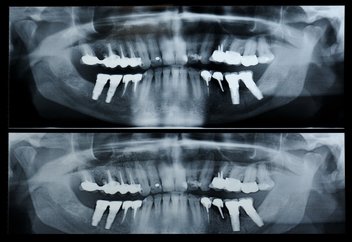

A panorex is a very impressive piece of imaging machinery in that it is capable of identifying many issues and structures that a normal x-ray is not. Initially you will sit in a chair with your chin on a small ledge. Once positioned in the machine, it will rotate around your entire head taking a full 360 degree view of the teeth, head, sinuses and bones.

The ability to view the full structure of your head as a whole is very informative to the dentist. It will allow us to see any potential problems and make sure that everything is functioning as it should be. The panorex is capable of viewing specific types of structural problems, infections or asymmetry among many others.